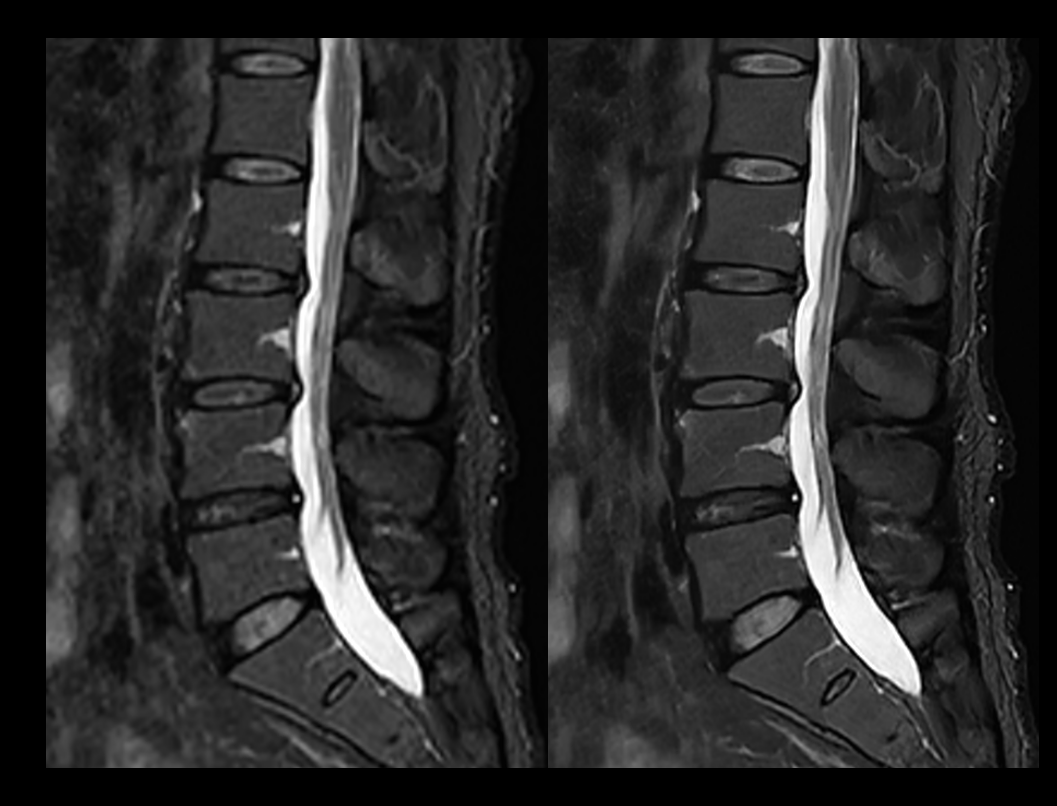

脊柱 T2W STIR

常规成像 (2:44 min) vs. uAIFI DeepRecon™ (2:44 min)

1.11×1.11×4 mm3